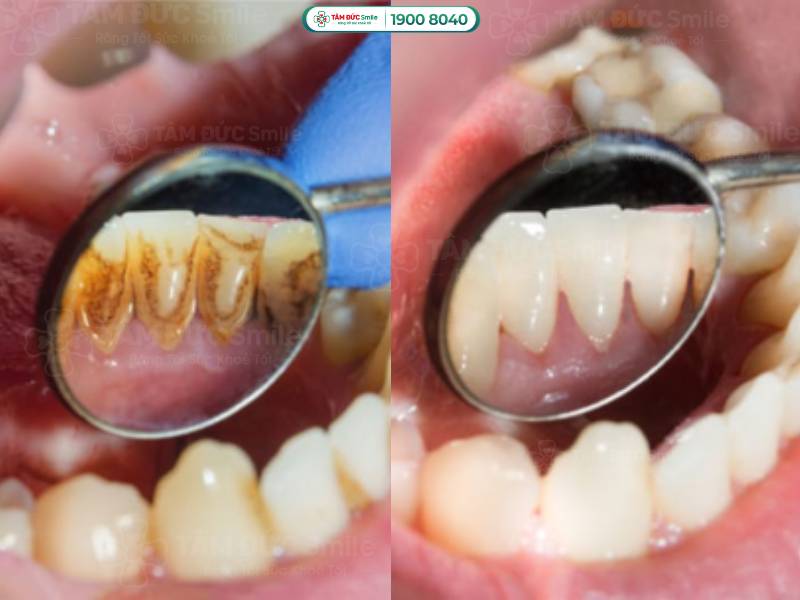

3.2.2. Cạo vôi răng định kỳ

Cao răng là môi trường sống lý tưởng của vi khuẩn gây ra bệnh nha chu. Do đó, bạn nên đến nha khoa 6 tháng một lần để cạo vôi răng, đồng thời khám tổng quát sức khỏe răng miệng.

Bạn nên đến nha khoa 6 tháng một lần để cạo vôi răng